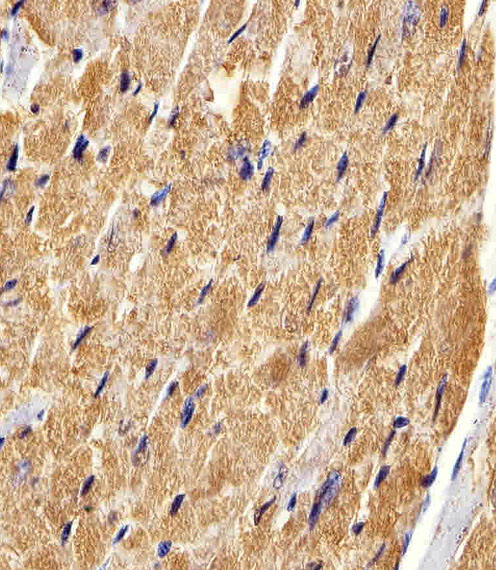

Facts about Fatty acid-binding protein, heart.

| Gene Name: | FABP3 |

FABP11; FABP3; fatty acid binding protein 11; fatty acid binding protein 3, muscle and heart (mammary-derived growthinhibitor); Fatty acid-binding protein 3; Fatty acid-binding protein 3, muscle; fatty acid-binding protein, heart; Heart-type fatty acid-binding protein; HFABP; H-FABP; H-FABPM-FABP; Mammary-derived growth inhibitor; MDGI; Muscle fatty acid-binding protein; O-FABP